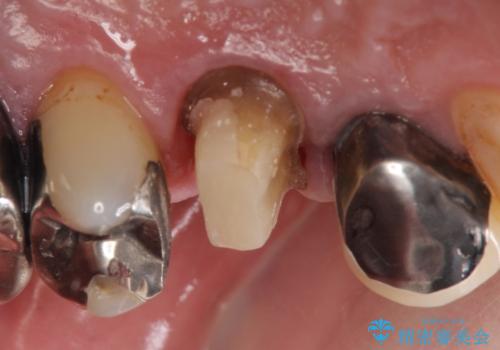

PGA(ゴールド)クラウン 脱離した銀歯の治療

- 古い銀歯が外れたので診て欲しいといらっしゃった方の症例です。

再根管治療後、PGA(ゴールド)クラウンによる補綴を行いました。

- PGA(ゴールド)クラウン…¥80,000、仮歯…¥10,000、ファイバーコア…¥20,000費用は治療当時の料金となります